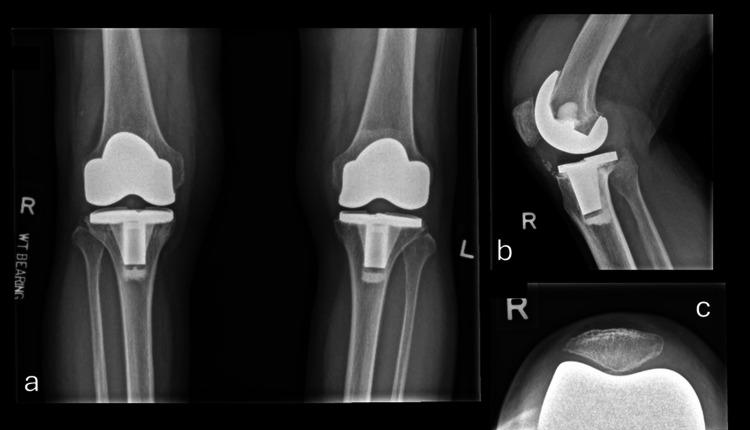

Particulate wear is a well-established cause of aseptic loosening and failure in joint arthroplasty. We aim to describe a case of cement-induced synovitis with the deposition of cement debris causing a distinct green-hued synovitis in a case of primary total knee arthroplasty (TKA). A 61-year-old lady presented to our clinic with right knee pain and swelling after undergoing bilateral total knee replacement four years ago at another institution. She was initially worked up by her primary surgeon and was symptomatically treated with non-steroidal anti-inflammatory medication (NSAID). However, her symptoms persisted and impaired her daily function. She presented with right knee effusion and decreased range of motion of the knee, as well as joint line tenderness. Further radiological investigations showed right knee tibial component implant loosening, with bone cement fragments in the anterior tibia. As such, the patient was counselled and underwent a revision surgery. Intraoperatively, there was extensive synovitis with prominent green pigment deposits. Excessive cement was noted in the femoral notch, causing wear of the liner pole. The tibia tray was also found to be loose, with no cement adherent to the tibia tray, and all the cement mantle seated on the tibia bone. Postoperatively, the patient made an uneventful recovery. She was able to range her knee from 10-130 degrees with no pain within 2 months. Direct wear from residual cement and micromotion at the tibia tray due to poor cementing technique during the primary surgery were important factors leading to severe cement wear and failure. This clinical case is a reminder of the importance of good cementing technique to ensure a good outcome in TKA.

颗粒磨损是关节置换术中无菌性松动和失败的一个公认原因。我们旨在描述一例水泥诱导的滑膜炎病例,在初次全膝关节置换术(TKA)中,水泥碎屑的沉积导致了一种独特的绿色滑膜炎。一名61岁女性四年前在另一家机构接受双侧全膝关节置换术后,因右膝疼痛和肿胀前来我院就诊。她最初由主刀医生进行检查,并接受了非甾体类抗炎药(NSAID)的对症治疗。然而,她的症状持续存在,影响了她的日常功能。她出现右膝关节积液、膝关节活动范围减小以及关节线压痛。进一步的影像学检查显示右膝胫骨部件植入物松动,胫骨前方有骨水泥碎片。因此,对患者进行了咨询并接受了翻修手术。术中发现广泛的滑膜炎,有明显的绿色色素沉着。在股骨切迹处发现过多的骨水泥,导致衬垫杆磨损。还发现胫骨托盘松动,胫骨托盘上没有骨水泥附着,所有骨水泥套都位于胫骨骨上。术后,患者恢复顺利。她能够在2个月内将膝关节活动范围从10度扩大到130度,且无疼痛。初次手术时由于骨水泥技术不佳导致的残留骨水泥直接磨损和胫骨托盘处的微动是导致严重骨水泥磨损和失败的重要因素。这个临床病例提醒我们良好的骨水泥技术对于确保TKA取得良好结果的重要性。